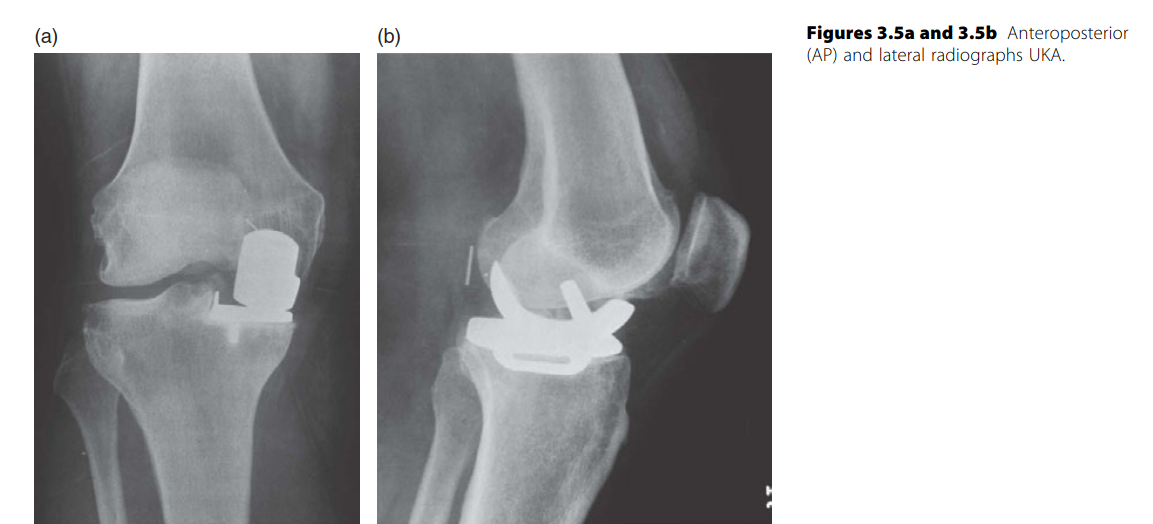

KNEE Structured oralexamination question4: Unicondylar knee arthroplasty ( UKA ) versus high tibial osteotomy…

KNEE Structured oralexamination question5: Unicondylar knee arthroplasty (UKA) versus total knee replacement …